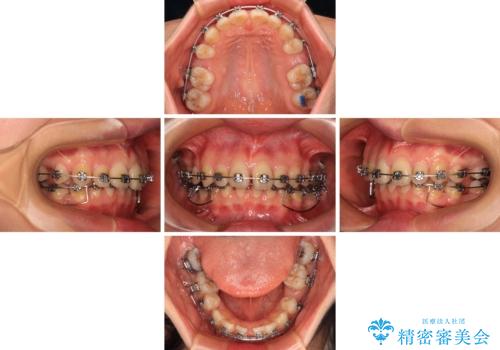

- メタルブラケット

- 治療期間

- 3年2ヶ月

上下臼歯の咬み合わせ改善には補助装置を、深い咬み合わせ改善にはユーティリティーアーチを活用し、ワイヤー装置にて矯正治療を行うこととしました。